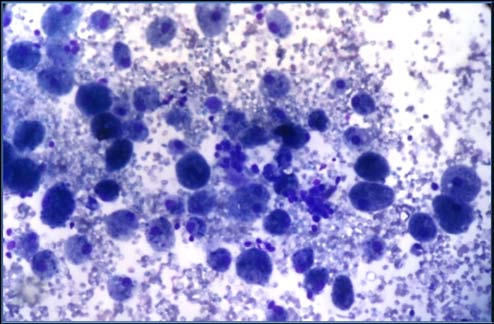

All the cases of thyroid swelling subjected to FNAC were performed by cytopathologist. Prior to procedure, palpation was carried out to note the mobility of the thyroid during swallowing and the presence of any enlarged cervical lymph node. The patients were made to lie supine with their necks stretched up. A 23-24 gauge needle was used, with non-aspiration technique in most cases and very few cases with aspiration technique by a 10 ml disposable syringe. Two or more passes at different sites were made in each case. No major complications like penetration injury to the trachea, laryngeal nerve, or hematoma were recorded. Slides were prepared from aspirated material. In the case of cystic nodules, the cysts' contents wereaspirated, centrifuged, and slides made from the sediment for cytological examination. The slides were stained with MayGrunwald Giemsa (MGG), Papanicolou [PAP] stain and Haematoxylin and Eosin (H&E) and examined under light microscope. The microscopic diagnosis was interpreted under guidelines laid down by TBSRTC including categories I to VI (table 1) after taking into account of all available clinical, radiology and other data. Whenever possible, further sub typing was given.The cytological diagnosis were correlated with clinical features, thyroid function tests, subjected to histopathological examination whenever possible.

Study includes total 160 cases of thyroid lesions which comprised of 140 cases (87.5%) of total. Published data suggest FNA has an overall accuracy rate around 75% in the detection of thyroid malignancy. Category II: It included most of the study cases with 140 cases (87.5%) of total. Age ranges with maximum number of cases were in 20-50 year age group. It consists of 'non-neoplastic' or 'negative for malignancy' cases like colloid goitre with 97 cases (69.29%), Thyroiditis with 36 cases (25.71%) and Adenomatoid goitre 7 cases (5%). All of these benign cases were just followed up and surgery was prevented.

Category II: Majority of lesions were benign mainly of colloid goitre 97 cases (69.29%) out of 140. In comparison to various studiesbenign category includes 60-70% [8] reason for that is we have goitre belt here. Similar findings were observed Unnikrishnan et al. [10] The chances of thyroiditis after reproductive age appeared minimal from this study.